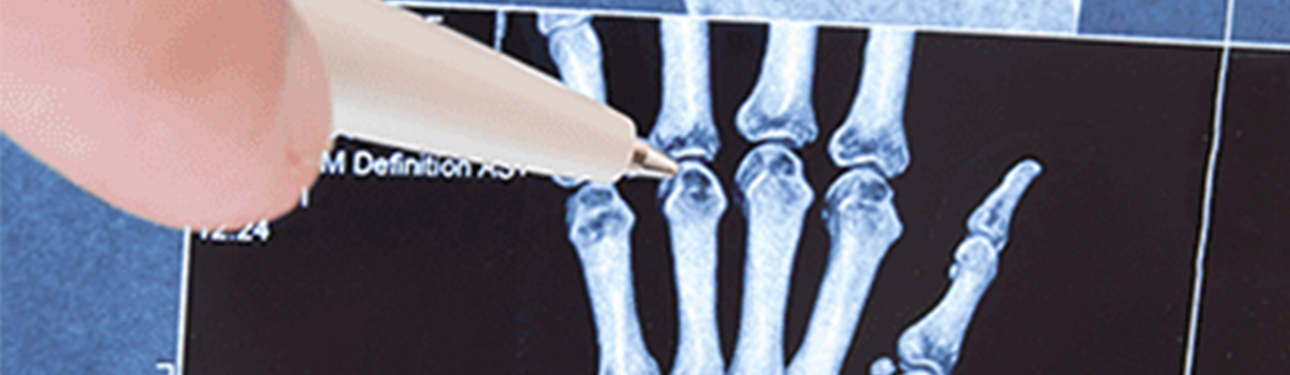

치료방향·진단 검사 증상이 뚜렷한 경우 쉽게 진단 가능하며, 통증의 위치 등으로 촉진할 수도 있습니다. 또한, 초음파 검사를 통해 건이 부어있거나 건 주위에 염증이 있는 것을 관찰할 수 있습니다.